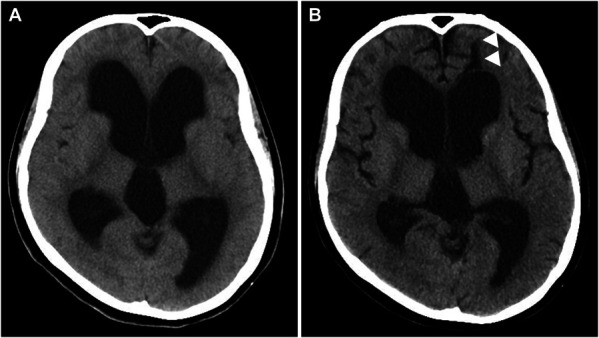

Clinical presentation: A 20-year-old woman presented with mild cognitive dysfunction and marked ventricular dilatation. She had no preoperative symptoms of intracranial hypertension, and her head circumference was more than 2 SDs above the 98th percentile. The aqueduct of Sylvius was entirely occupied by a neoplastic lesion with 2 periventricular nodules at the wall of the third ventricle and anterior horn of the right lateral ventricle. She was treated successfully with endoscopic tumor resection followed by chemotherapy, and the patency of the aqueduct of Sylvius was secured throughout the duration of treatment.